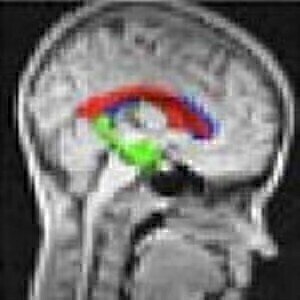

The team of Max Planck Society scientists have established a number of techniques to accelerate the process in an attempt to overcome the limitations of MRI.

The scientists looked at encoding spatial information radially, removing its sensitivity to movement as a result.

Meanwhile, they developed a mathematical technique to replace missing data - meaning less information is required to construct a full image.

This means scans can be completed proportionately faster - for example, 20 times faster if just five per cent of the imaging information is required.